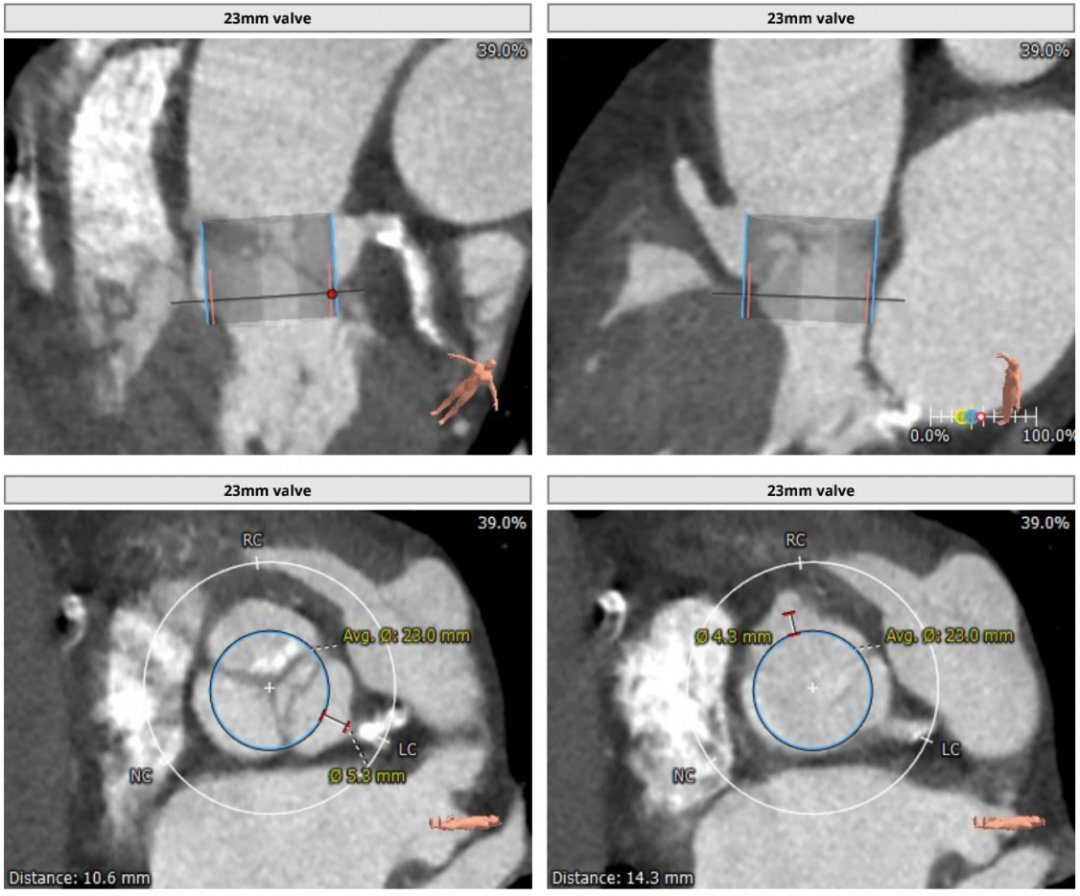

近日,武汉大学人民医院江洪教授团队成功挑战主动脉瓣严重狭窄合并钙化病变,顺利完成SAPIEN 3球囊扩张式瓣膜植入。在团队成员紧密配合下,克服患者弥漫钙化病变,顺畅完成过弓、跨瓣及释放操作,实现了手术的圆满成功。这是武汉大学人民医院首例应用SAPIEN 3瓣膜完成的TAVR。 患者基本情况 患者女性,78岁,既往有劳累性心绞痛,三支血管病变,右冠、前降支均存在大量钙化及狭窄,主动脉瓣严重狭窄伴中度钙化。 影像学检查结果 术前CT结果显示,主动脉瓣口面积373.6mm²,瓣环平均直径22.3mm,瓣环周长70.5mm;LVOT面积287.2 mm²,LVOT平均直径19.9mm;心夹角55°;左冠开口高度14.8mm、右冠开口高度16.2mm。 术前CT检查结果 手术策略讨论:

瓣膜选择软件分析报告